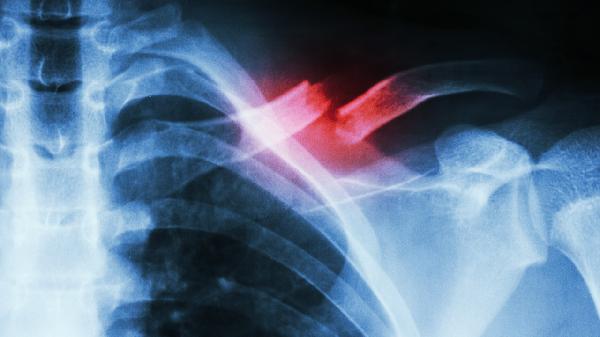

严重骨性畸形或创伤后错位愈合需手术矫正。常见术式包括锁骨截骨矫形术、钢板内固定术等,术后需石膏固定4-6周。手术适应证包括影响肩关节功能、压迫神经血管或畸形进行性加重等情况。

日常应避免单侧负重和重复性不对称动作,睡眠时保持仰卧位。青少年建议每日进行扩胸运动、肩部环绕等对称性锻炼,补充足量钙质和维生素D。成人出现进行性加重的锁骨不对称或伴随疼痛、活动受限时,应及时就诊骨科或康复科,通过X线、CT等检查明确病因。矫正过程中需定期评估效果,根据医生建议调整治疗方案。